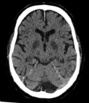

Rozlane uszkodzenie mózgu jest zasadniczym elementem zespołu poresuscytacyjnego, opisywanym u 30–80% chorych z pozaszpitalnym nagłym zatrzymaniem krążenia (NZK), odpowiadającym za wysoką śmiertelność oraz deficyty poznawcze i neurologiczne prowadzące do niepełnosprawności. Różnorodność i dynamika objawów oraz możliwości rehabilitacji pacjentów po NZK są słabo poznane.